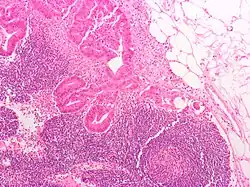

Local cancer in many parts of the body can cause lymph nodes to enlarge because of tumorous cells that have metastasised into the node.[36] Lymph node involvement is often a key part in the diagnosis and treatment of cancer, acting as "sentinels" of local disease, incorporated into TNM staging and other cancer staging systems. As part of the investigations or workup for cancer, lymph nodes may be imaged or even surgically removed. If removed, the lymph node will be stained and examined under a microscope by a pathologist to determine if there is evidence of cells that appear cancerous (i.e. have metastasized into the node). The staging of the cancer, and therefore the treatment approach and prognosis, is predicated on the presence of node metastases.